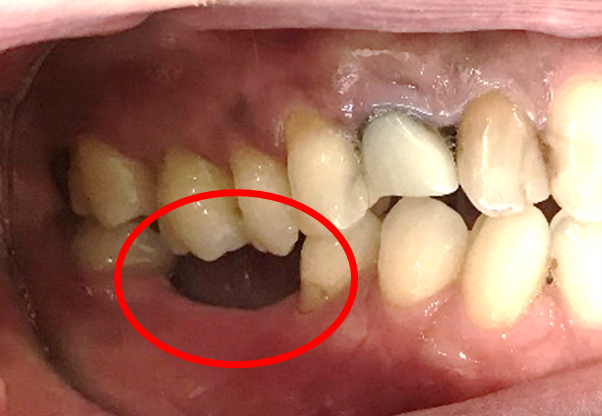

【インプラント埋入前】

冠はブリッジを切断しただけで取れてきました。軟化象牙質を取り除いたところ、歯根しか残っていない状況で保存できるかどうかのぎりぎりのところでした。